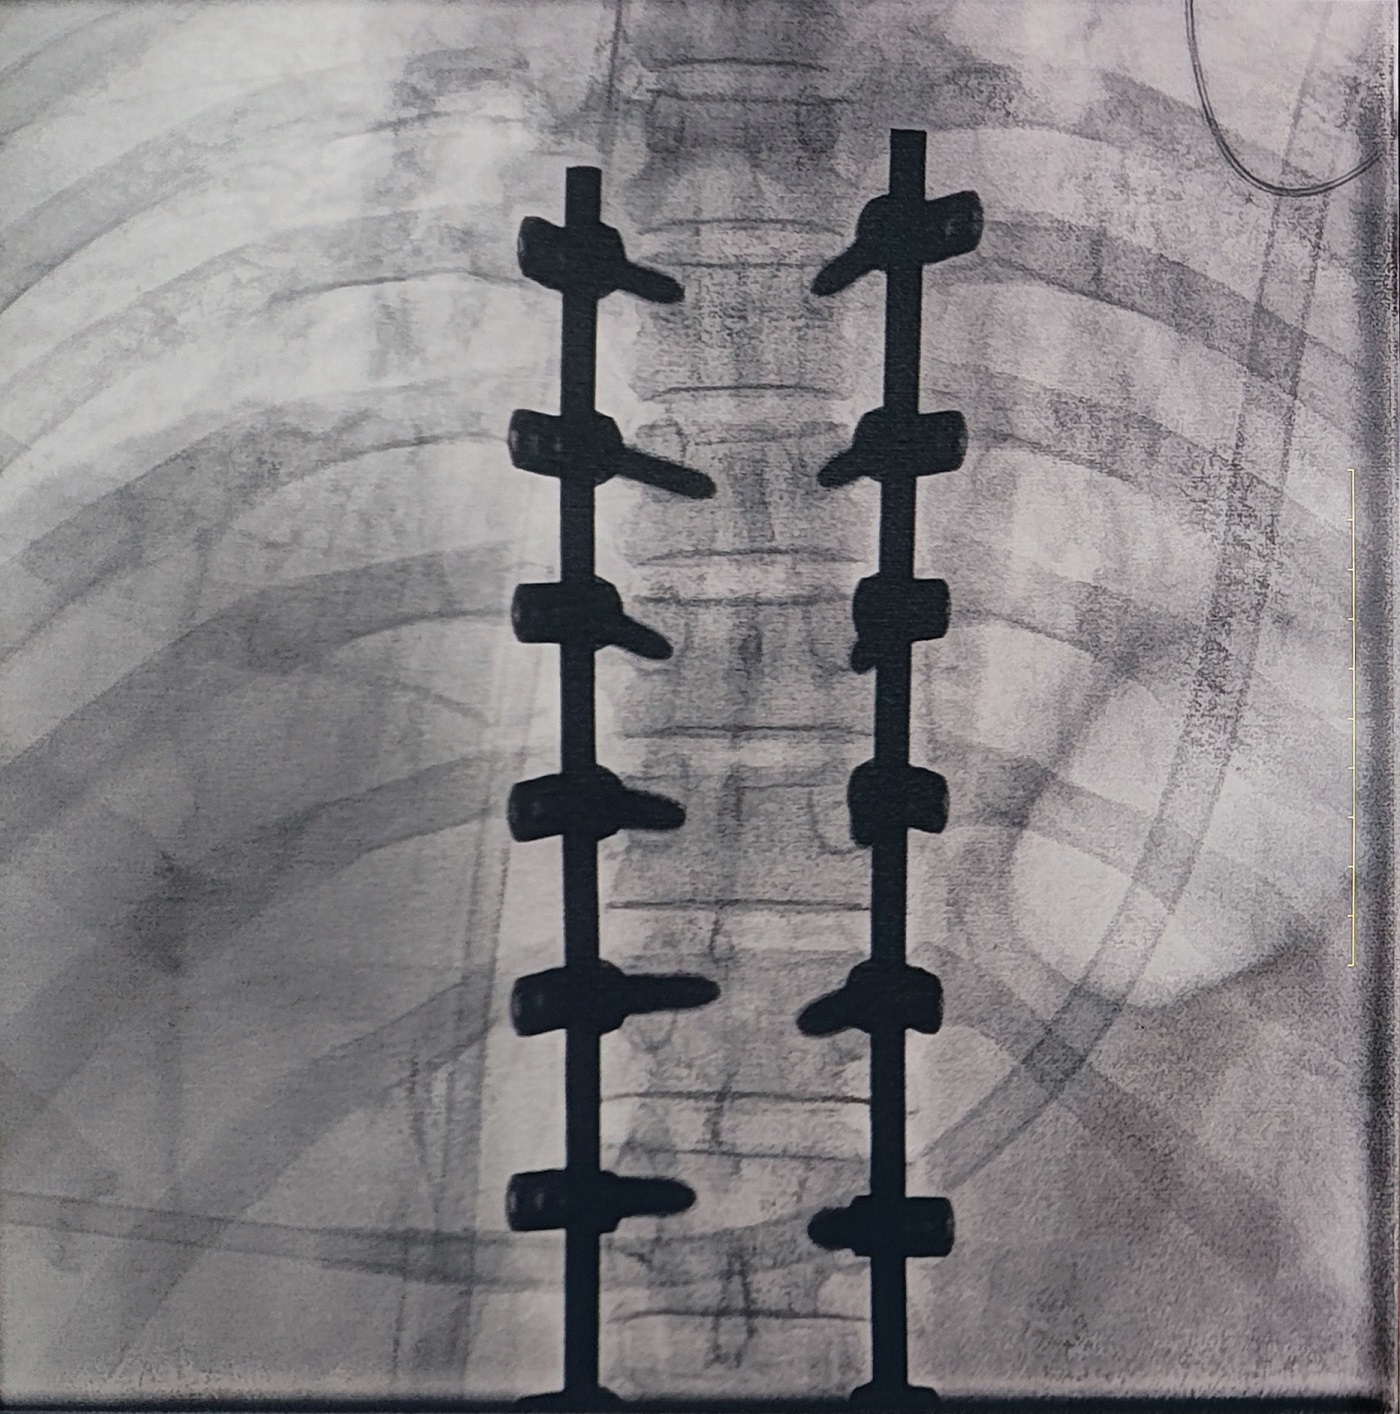

一場脊柱手術(shù)中,醫(yī)生需要拍攝跨越7個(gè)節(jié)段的脊柱影像,由于曝光的視野較大,常規(guī)視野的C形臂通常需要拍攝2-3次,普愛醫(yī)療大平板一體式C形臂30CM*30CM的“大視野”,輔助醫(yī)生一次性完成了7個(gè)節(jié)段的拍攝。最終,醫(yī)生在高清影像的輔助下完成了14枚螺釘?shù)木珳?zhǔn)定位、置入。

大視野,不僅意味著醫(yī)生可以更快,獲取更全面的影像信息,做出精準(zhǔn)判斷,無需多次拍攝定位,也顯著地降低了患者接受的輻射劑量。